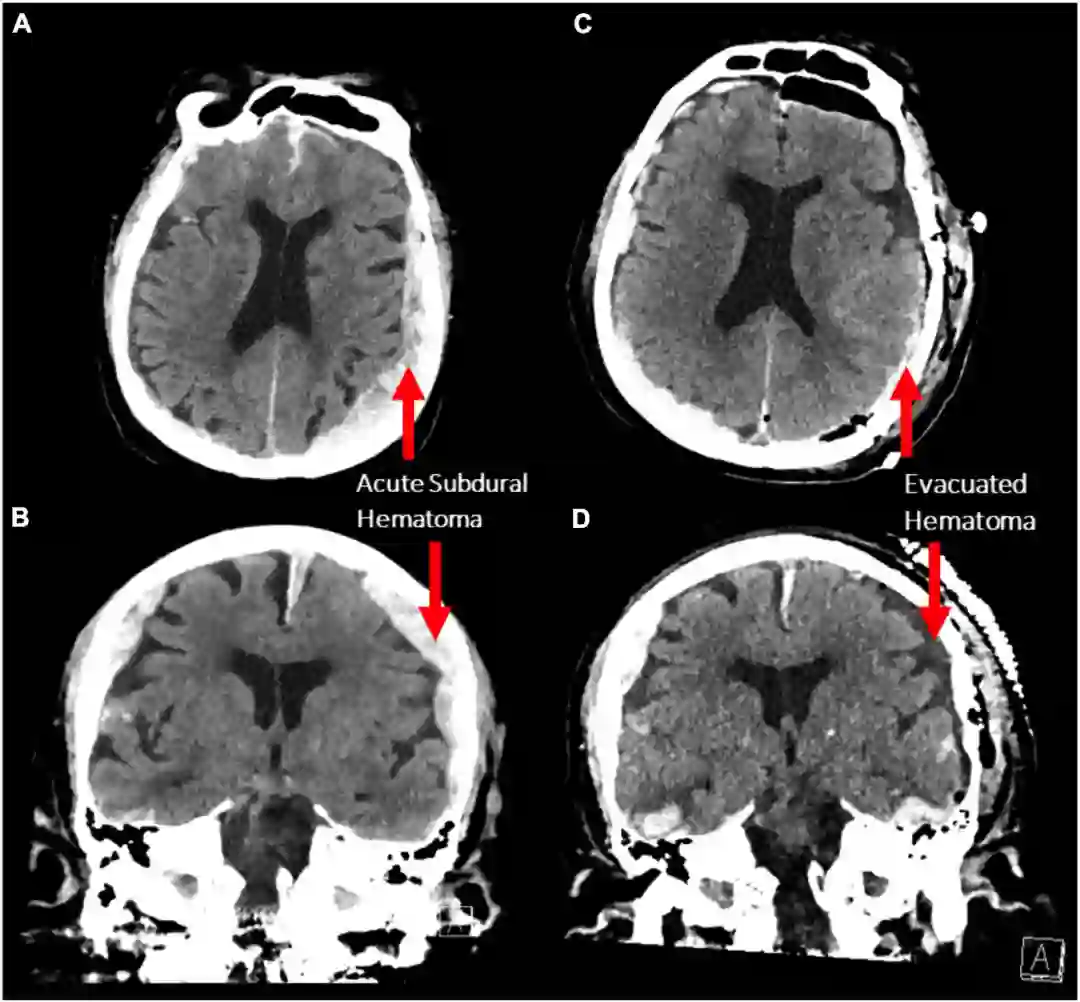

开颅减压术后,左侧硬膜下血肿已被清除